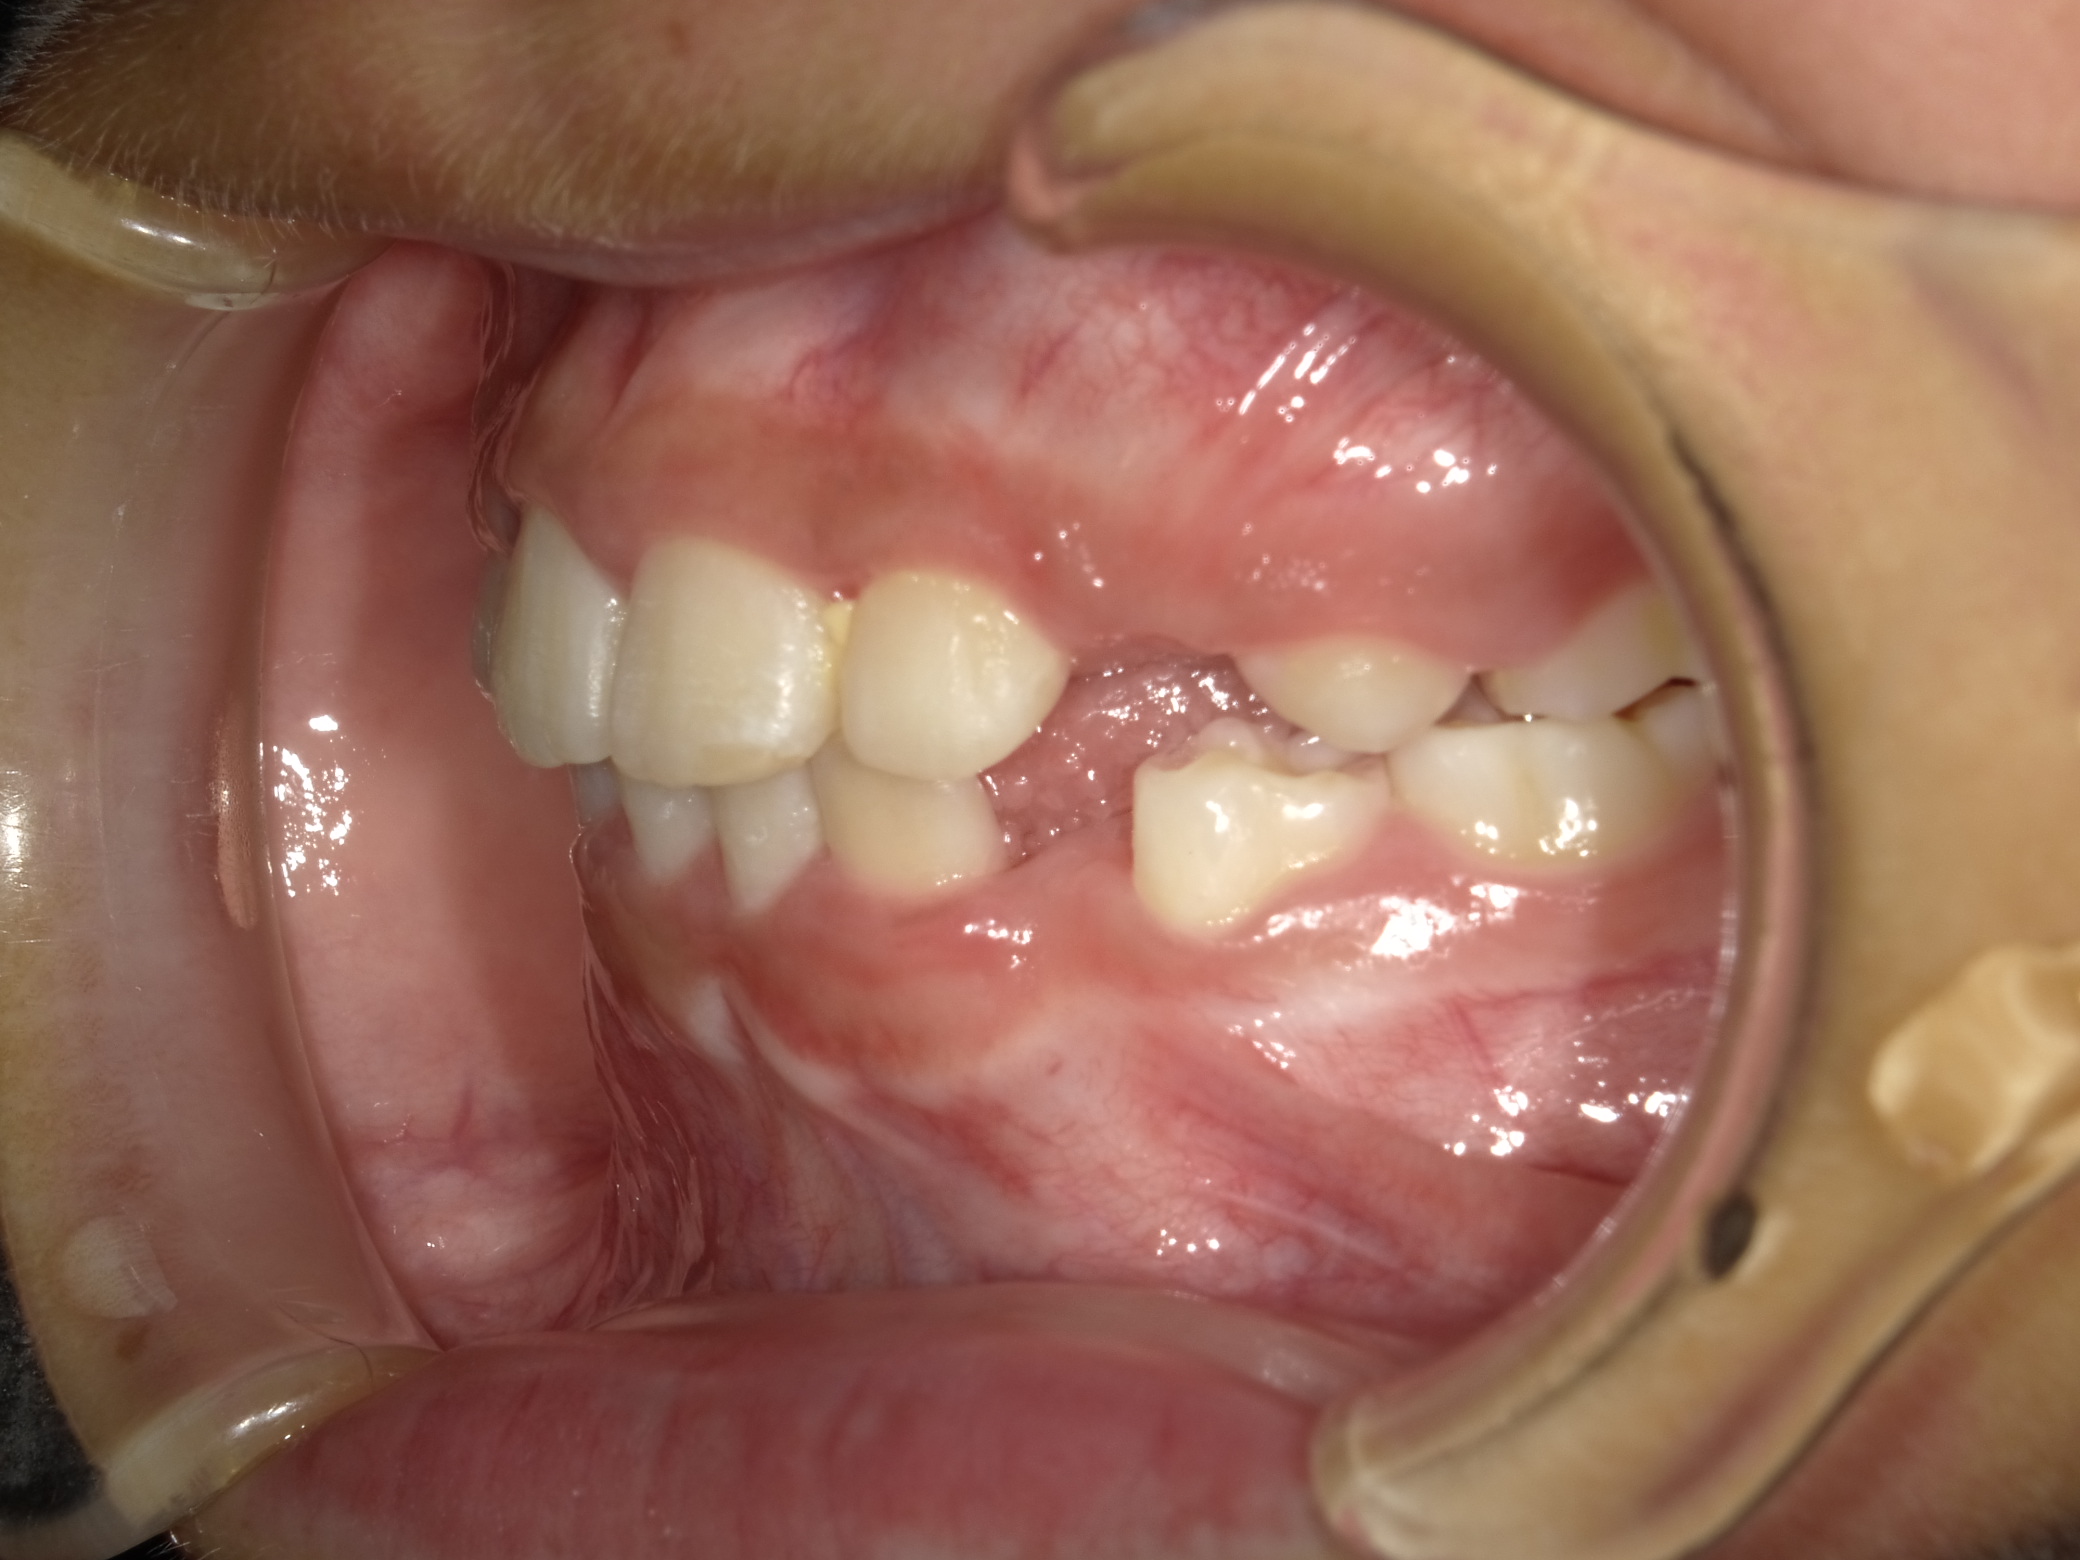

右横

| 治療内容 | インビザライン・ファースト |

| 治療詳細 | スペース不足や交叉咬合を整えるために、歯の表面にアタッチメント(白い突起)をつけ、治療を行いました。 |

| 患者情報 | 9歳 男性 予防矯正から移行 |

| 主訴 | 永久歯は生えそろう十分なスペースがない 一部分だけかみ合わせが反対 |